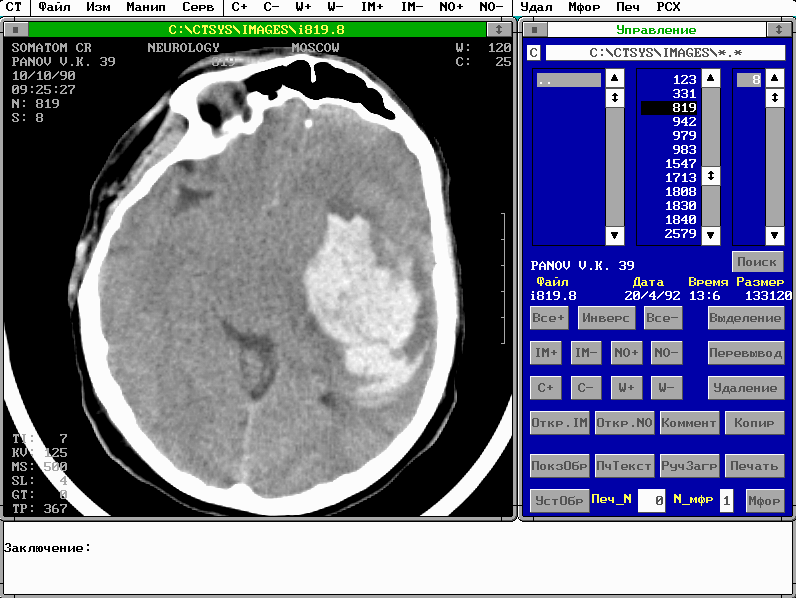

После инсталляции системы, проводимой разработчиками, она находится в рабочем директории c:\ctsys\exe. Надо войти в него и выполнить команду ct_work.bat. На экране дисплея появится нечто, похожее на нижеприведенную иллюстрацию:

Это конфигурация для работы с изображениями. На рисунке видны два главных окна системы: окно Управление (справа) и окно Изображения, с изображением среза, полученного на рентгеновском томографе.